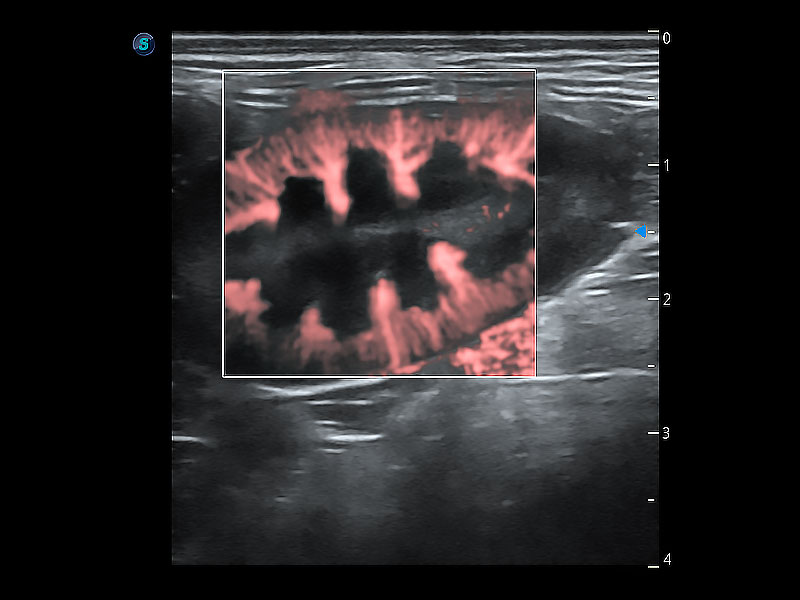

在传统二维血流成像的基础上,呈现血流的立体感,具有动感的生命力之美。即便是微小的血管也能轻松应对,提高了血流的视觉敏感性。